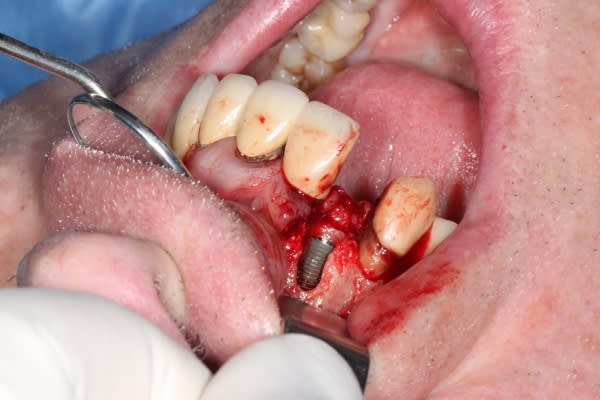

juste pour le plaisir

un petit dernier mis en fonction la semaine dernière

1 pbr75u - Eugenol

2 wlbqqs - Eugenol

3 soqqmc - Eugenol

4 peblmt - Eugenol

5 ebbipt - Eugenol

Img 8465 fqhxid - Eugenol

Juste une remarque sur tes photos Michael, puisque sur la chirugie tu maitrises parfaitement : irrigues ton site avant de prendre une photo et enlèves les taches de sang sur les dents adjacentes, ça ne change en rien la qualité de ton travail, mais c'est plus propre et plus agréable à regarder.